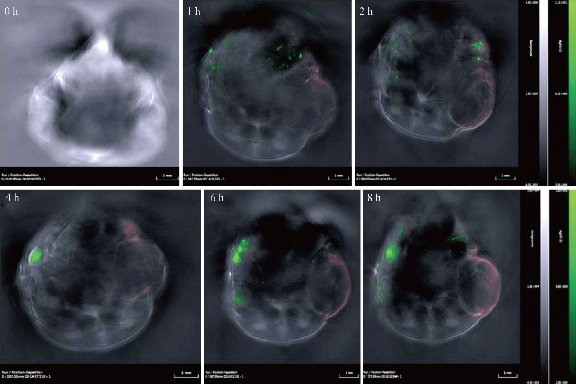

In order to visualize EGFR-Au@AgNR nanotags in vivo, gastric cancer-bearing nude mice model were prepared. We also compared the light absorbance of Au NRs, Au@Ag NRs, Hb and HbO2 by spectrophotometer, as shown in Fig. 8, Au@Ag NRs owns strongest absorption peak, locates in 756 nm. Finally, we selected 808 nm laser as the light source. The prepared EGFR-Au@AgNRs-DTNB nanoprobes were injected into gastric cancer-bearing nude mice via tail vein; the photoacoustic signal were obtained by MSOT apparatus. As shown in Fig. 9. At 4 h post-injection, tumor boundary became clearer; at 8 h post-injection, the tumor boundary became clearest, which fully demonstrate that prepared nanoprobes can identify tumor boundary by photoacoustic imaging, which should be the first report.

Fig.9 Photoacoustic imaging of gastric cancer site at 0h, 1h, 2h, 4h, 6h, 8h post-injection by OMST.